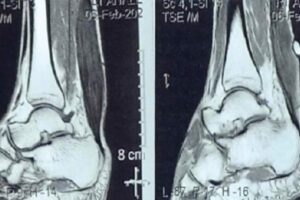

Non-Unions of the Hind Foot

Hind foot non-unions are a complex orthopedic challenge that clinicians face, particularly due to the unique anatomy and weight-bearing responsibilities of this part of the foot. Non-unions occur when a fracture fails to heal nine months after injury or shows no radiographic improvement over a consecutive 3-month period. This condition is not only painful but can also severely impact mobility and quality of life.

By Zeeshan Husain, DPM, FACFAS, FASPS